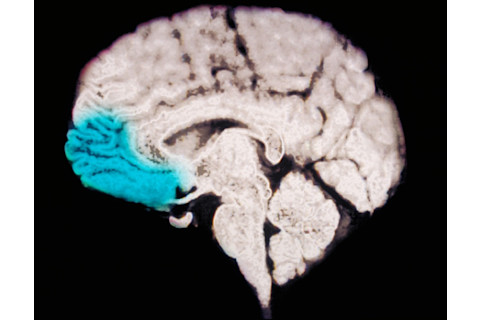

在过去的二十年里,米勒一直致力于理解工作记忆背后的机制,他认为关键在于大脑的额叶皮层。对大脑前部这层薄薄的神经元网络的深入了解,或许能解答困扰科学家们几代人的问题。它可能还有实际用途。

此 MRI 扫描中突出显示的额叶皮层,在工作记忆——大脑的注意力与决策黑板——中起着至关重要的作用。Scott Camazine 和 Sue Trainor/Science Source